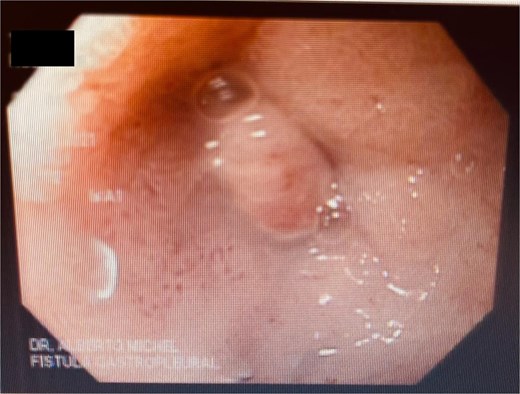

A 48-year-old female without comorbidities underwent vertical sleeve gastrectomy for grade II obesity, developing a leak in the upper third of the sleeve, presenting with a productive cough. Endoscopy revealed a 15 mm fistula (Fig. 6). EVAC therapy was initiated with changes every 3–5 days (Fig. 7). The patient showed slow evolution, developing an intragastric abscess and productive cough. After nine changes over 45 days, endoscopy showed complete resolution of the fistula (Fig. 8).

Initial endoscopy shows a fistulous defect below the gastroesophageal junction.

A sponge replacement is performed, revealing a fistulous opening with granulation tissue.

Upon removing the EVAC sponge, we can observe a clean cavernous cavity with minimal fibrin and granulation tissue.